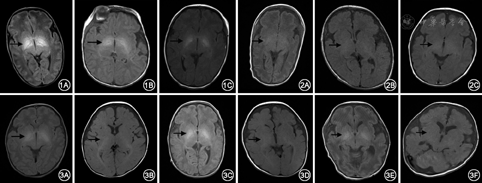

186例新生儿中138例(74.2%)出现GP及STN出现对称性T1WI高信号(图1,图2),其中正常新生儿中68例出现(74.7%,68/91),病变组新生儿70例出现(73.7%,70/95),二者发生率差异无统计学意义(χ2=0.026,P=0.871);15例有随访MRI的新生儿均观察到GP及STN对称性T1WI高信号,于1~5个月后复查头颅MRI显示GP及STN高信号均消失(图3),而且小儿发育及神经系统体格检查均正常。

TCB、胎龄和检查时年龄在GP及STN有无高信号的新生儿间差异有统计学意义[TCB:(132±62)比(91±55) μmol/L (t=3.935, P<0.01);胎龄:(36.0±2.6)比(34.8±3.4)周 (t=2.263, P=0.027);检查时年龄:(9±5)比(19±7) d(t=8.992, P<0.01)]。性别、窒息及高胆红素血症在GP及STN有无高信号的新生儿间差异无统计学意义[性别∶男/女高信号发生率,71.8%比77.6% (χ2=0.793, P=0.373);窒息史:有无窒息史间高信号发生率,67.9%比75.3% (χ2=0.691, P=0.406);高胆红素血症:有无高胆红素血症的高信号发生率,71.1%比75.2% (χ2=0.295, P=0.587)]。Logistic回归分析显示新生儿MR检查时年龄是GP及STN对称性T1WI高信号的危险因素,且呈负相关(OR=0.795,95%可信区间0.739~0.856,P<0.01);而TCB和胎龄不是危险因素。出生后年龄与GP及STN T1WI高信号相关性的ROC曲线见图4,曲线下面积为0.878,并根据Youden指数确定年龄分界值为20 d,≤20 d内的新生儿出现GP及STN对称性T1WI高信号的发生率为83.2%,>20 d的发生率为16.0%,两者差异有统计学意义(χ2=51.084,P<0.01)。

本组186例新生儿中138例(74.2%)出现GP及STN高信号,且在正常及病变组新生儿的发生率差异无统计学意义。单因素分析显示性别、窒息史、病理性黄疸(高胆红素血症、核黄疸)在双侧GP及STN有无T1WI高信号新生儿间差异均无统计学意义,胎龄、出生后年龄及检查3 d内TCB水平在两者间差异有统计学意义。Logistic回归分析显示出生后年龄与新生儿MR检查时GP及STN出现T1WI高信号呈显著负相关,而胎龄、检查3 d内TCB水平不是GP及STN出现T1WI高信号的危险因素。此外,本组15例新生儿经过1~5个月后复查头颅MRI, GP及STN对称性T1WI高信号均消失,且复查时15例小儿均无神经系统发育异常表现。因此本研究结果表明,新生儿GP及STN出现对称性T1WI高信号是与年龄相关的一过性现象,不能作为核黄疸、新生儿缺血缺氧性脑病的特异性MRI征象。本研究的结果与Taoka等[7]报道一致。Taoka等对观察对象进行2年的随访,无论GP及STN有无对称性T1WI高信号均发育正常。本研究还通过ROC曲线确定GP及STN对称性T1WI高信号消失的年龄分界值为20 d,在<20 d和>20 d的新生儿,GP及STN出现对称性T1WI高信号发生率差异有统计学意义。